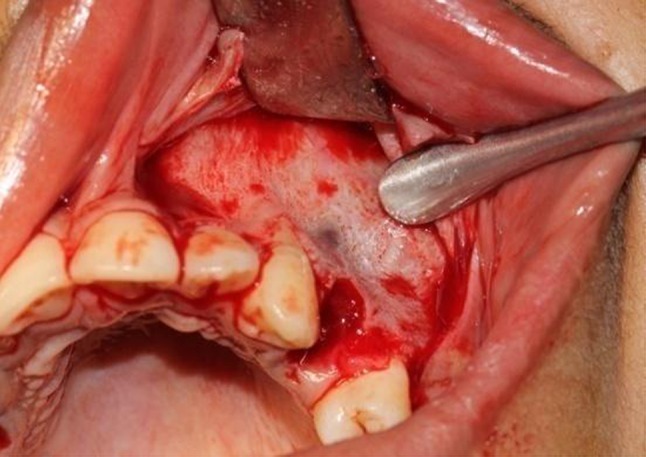

For DAD side crevicular incisions were made extending from the mesial interdental papilla of the first molar to the mesial interdental papilla of the lateral incisor with vertical releasing incision on either side into vestibule to raise mucoperiosteal flap 6 mm above the canine and first premolar to allow for the planned osteotomy (Fig. 5). Cortical holes were made in the alveolar bone with a small, round, carbide bur from the canine to the second premolar, curving apically to pass 3–5 mm from the apex (Fig. 6) which depends upon the anatomic limitations i.e. distance of sinus floor from the apex of the canine or distance of the nasal floor from the canine apex. A thin, tapered, fissure bur was used to connect the holes around the root. Fine osteotomes were advanced in the coronal direction. The first premolar was extracted and the buccal bone removed between the outlined bone cut at the distal canine region anteriorly and the second premolar posteriorly. Larger osteotomes were used to fully mobilize the alveolar segment that included the canine by fracturing the surrounding bone around its root off the palatal cortex. The buccal and apical bone at the buccal aspect were eliminated and smoothened out between canine and 2nd premolar as they may offer a bony interference during the distraction process. The palatal shelf was preserved, but the apical bone near the sinus wall was removed, leaving the sinus membrane intact to avoid interferences during the active distraction process. Osteotomes along the anterior aspect of the canine were used to split the surrounding bone around its root from the palatal cortex and neighbouring teeth. The transport dentoalveolar segment that included the canine also included the buccal cortex and the underlying spongy bone that covered the canine root, leaving an intact palatal cortical plate and the bone around the apex of the canine (Fig. 7). The surgical wound on both side was closed with non-absorbable sutures and antibiotic, nonsteroidal anti-inflammatory drugs were prescribed for 5 days. The surgical procedure lasted approximately 90 min.

Fig. 7.

Separated dentoalveolar segment on the DAD side